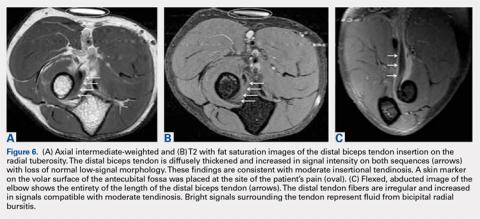

In distal biceps tendinosis, increased signals of thickened tendon fibers at the radial tuberosity are evident without focal discontinuity7,8 (Figures 6A-6C). Patients may display attenuation of the distal tendon fibers or adjacent fluid distension representing bicipitoradial bursitis (Figures 7A, 7B).MRI is useful in assessing the distal biceps tendon in the postoperative setting to evaluate the integrity of a repaired tendon. Cortical fixation button technique for repair creates minimal susceptibility artifacts on MRI. Postoperative MRI typically demonstrates a transverse hole drilled through the proximal radius at the site of the tuberosity with a cortical fixation button flush against the posterior radial cortex (Figures 8A-8D).